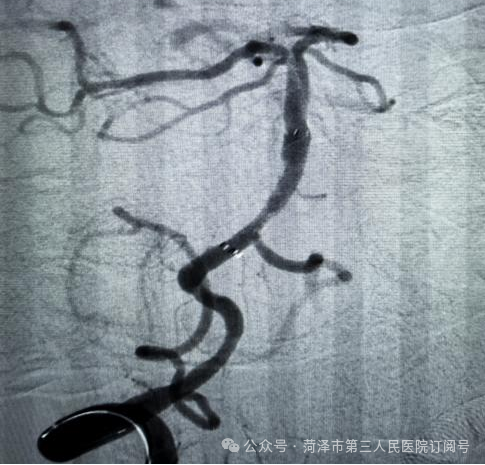

介入科主任司二旺接到紧急通知,第一时间带领团队与神经内五科共同讨论手术方案,并同步开展术前评估等,最大限度争取抢救时间。术中,介入团队凭借精湛的技术,进行了取栓、支架置入等操作,成功将血管内的血栓取出,让闭塞的血管再通,为患者赢得了宝贵的生机。